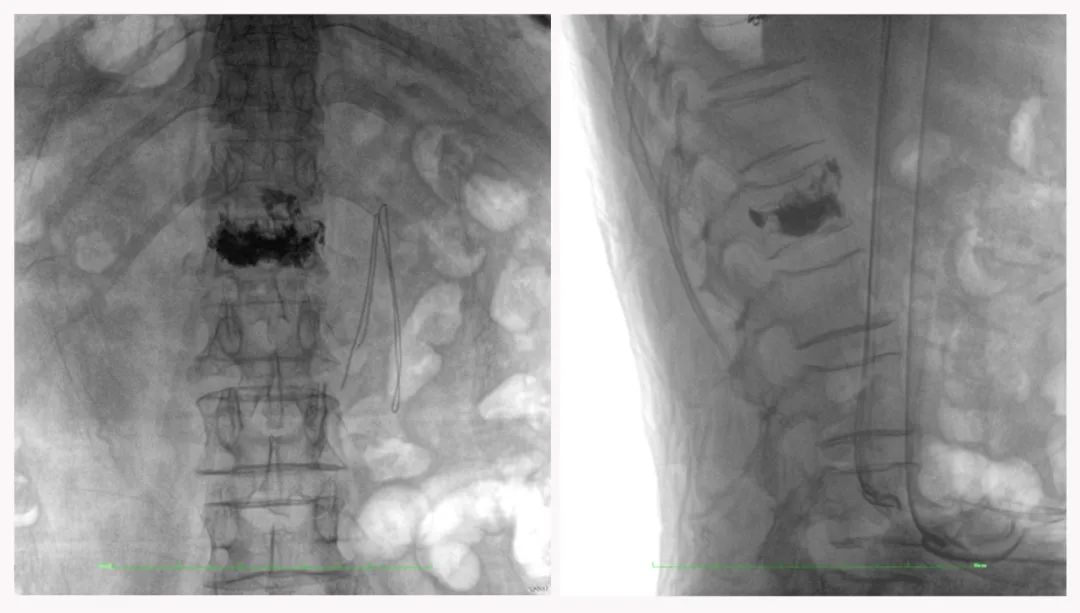

病例3:超声支气管镜下肺活检(80岁)

三维C形臂还可以创新性地应用在呼吸介入领域。例如,在经皮穿刺或经支气管镜肺结节活检、定位、消融等场景中,用于确认工具是否到达病灶、消融范围是否完全覆盖病灶等。

二维影像无法准确判断工具是否到达病灶

三维各切面影像都显示工具达到病灶内